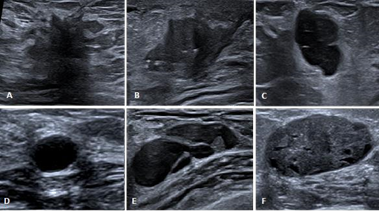

Breast ultrasound is usually used conjointly with mammography, particularly in patients with dense breasts. It was first used to differentiate solid from cystic lesions during the 70’s.4,10 Nowadays, with technological advancement, modern ultrasound devices are able to characterize breast lesions (Figure 2) and to improve diagnosis of breast cancer with a negative predictive value of 99.5% and a sensitivity of 98.4%,13 thus avoiding unnecessary biopsies. In spite of its technical improvements, ultrasound still bears some limitations: first of all, it is an operator-dependent modality, therefore physicians’s experience may play a crucial role in disease detection; secondly, it is unable to detect microcalcifications, one of the early hallmarks of ductal carcinoma in situ (DCIS), which is believed to herald infiltrating ductal carcinoma.4,10,13

Figure 2 A. Hypoechoic lesion with spiculated borders associated with a hyperechoic halo and an acoustic shadow. B. Hypoechoic lesion with irregular and angulated borders. C. Well delimited hypoechoic lesion presenting a “taller than wide” shape. D. Simple cyst presenting as a well delimited anechoic lesion with posterior enhancement. E. Complex cyst with septations and mural nodule. F. Well delimited hypoechoic lesion containing small cysts with ovoid shape.